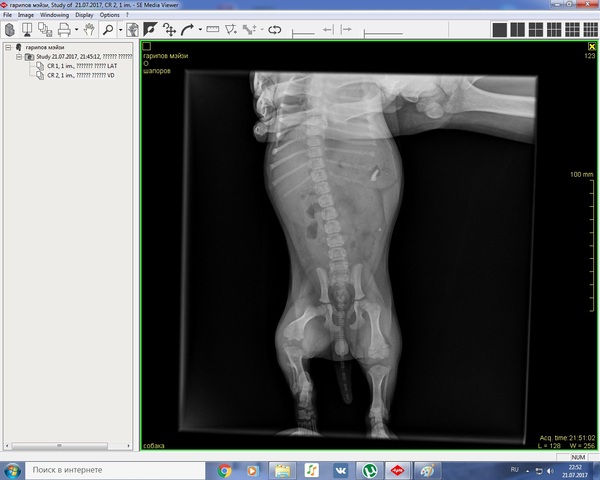

Не уследили, этого не отнять, комментарии на эту тему излишни. Собака сразу была отвезена в вет клинику, сделан рентген. Диагноз: перелом задней правой ноги. Предложили два варианта: лангета (которую сделали сразу) или операция под наркозом и вживление металлоконструкции. Говорят что нога может зажить не правильно и собака останется хромой. Операция также не даст 100% результата. Вопрос в том: стоит ли делать операцию (финансовый вопрос волнует сильно, но если действительно надо - буду искать варианты)? С лангетом часто кости срастаются не правильно? Как правильно ограничить собаку? Сказали посадить ее чуть не в переноску и держать там две недели почти безвылазно. С выставками придется распрощаться сразу?